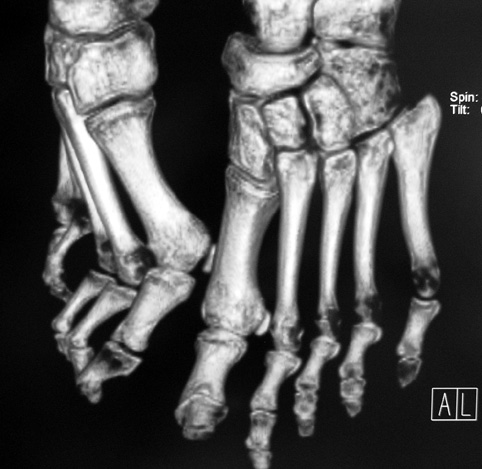

El parmağı (metakarp) ve ayak parmağı (metatars) kısalıkları doğuştan tek başına, geniş bir sendrom grubuyla birlikte, travma sonrası, Freiberg hastalığı (avasküler nekroz) sonrası görülebilir.

Doğuştan metakarp ve metatars kısalığının görülme sıklığı 1/1000’den azdır. Kadınlarda erkeklere göre 5 kat daha fazla görülür ve sıklıkla (%72) iki taraflıdır. En sık 4. parmak tutulur. Bu tür olgularda sorunun nedeni tam olarak bilinmemekle brlikte deformitenin genellikle epifiz plağının erken kapanmasından kaynaklandığı düşünülmektedir.

Doğuştan metakarp ve metatars kısalıklarının redavisi için pek çok teknik tanımlanmakla birlikte en çok akut uzatma sonrası kemik uçlarına greft konması ve distraksiyon osteogenezi (kallotasis) kullanılmaktadır. 1 cm.den daha fazla uzatma gereken olgularda kallotasis yöntemi önerilmektedir. Kliniğimizde de metatars ve metakarp uzatma için unilateral eksternal fiksatör ve sirküler eksternal fiksatör yardımıyla distraksiyon osteogenezi yöntemi tercih edilmektedir.